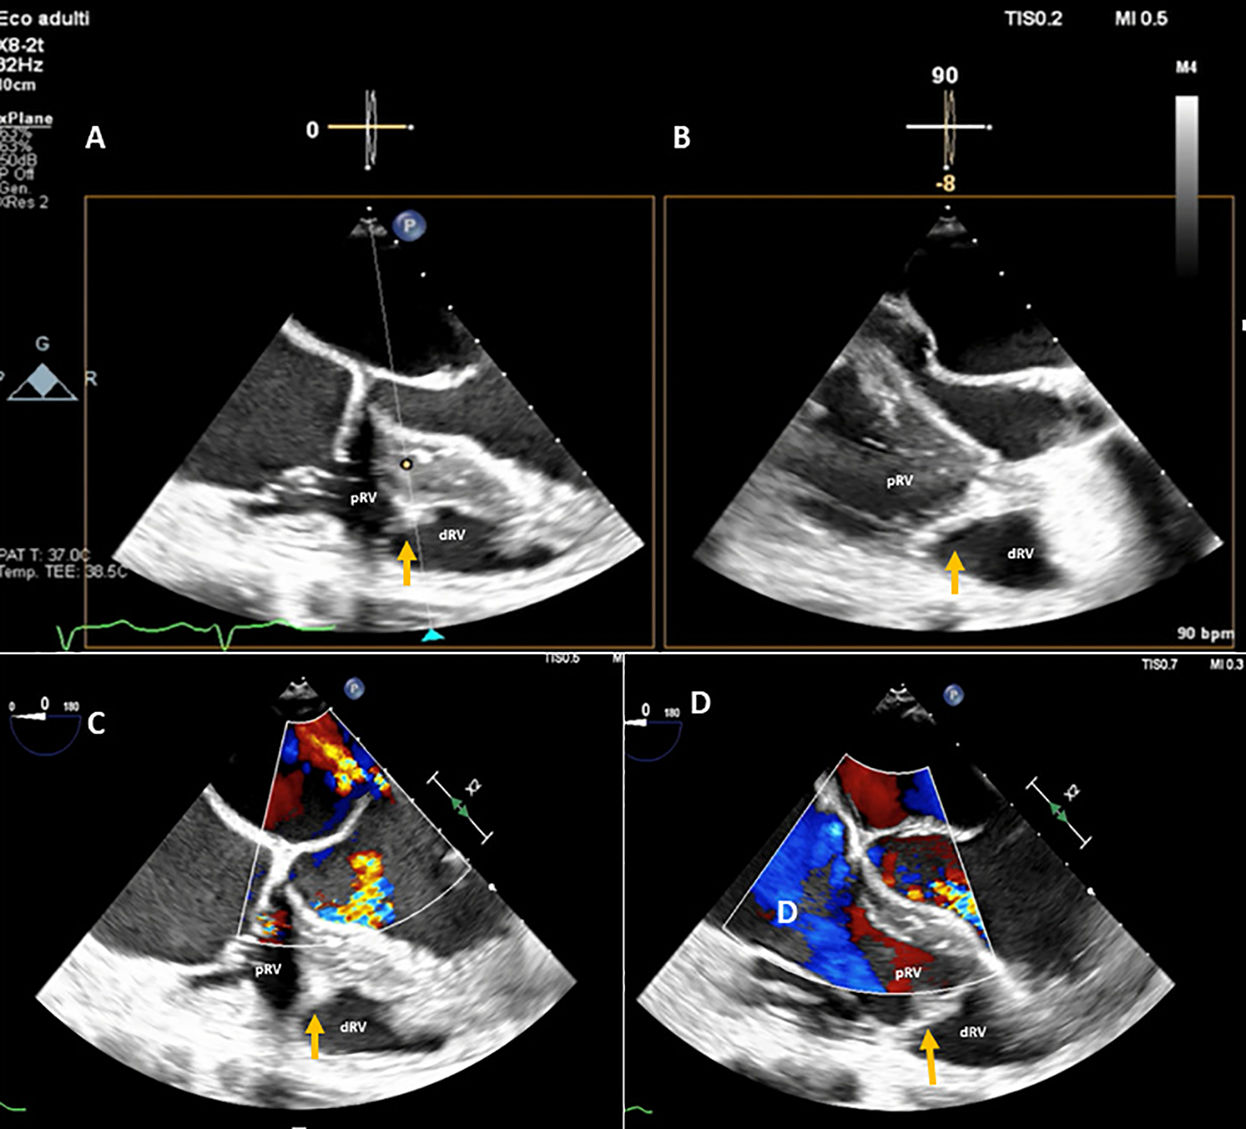

Figure 3

A DCRV created by an anomalous muscle band (orange arrow) diagnosed with TEE by the presence of a proximal high-pressure region under the tricuspid valve and a low-pressure distal region near the pulmonary valve outflow tract. (A,B) TEE transgastric RV inflow-outflow view (double orifice). (C,D) TEE color Doppler mid-esophageal four-chamber view focused on the RV. pRV, proximal right ventricle; dRV, distal right ventricle.